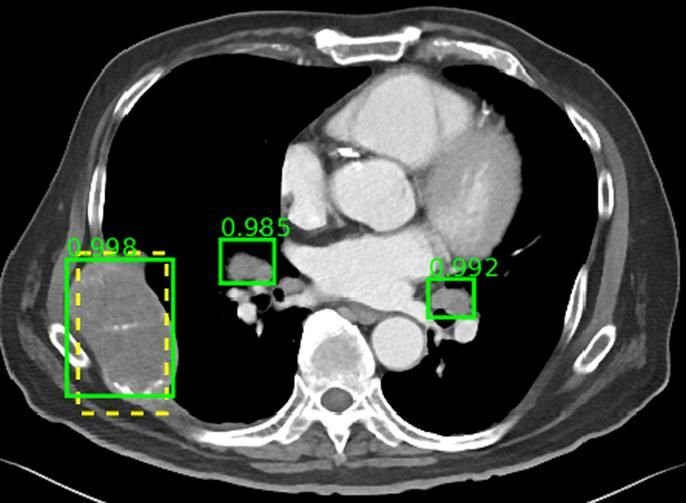

Percepción de la inteligencia artificial en la comunidad radiológica argentina

Aunque el grado de conocimiento acerca de la IA en la comunidad radiológica argentina es moderado, encontramos un alto interés y expectativas, y un bajo nivel de miedo o rechazo. Las sociedades radiológicas argentinas deberían desarrollar cursos de formación en IA. Rev Argent Radiol. 2024